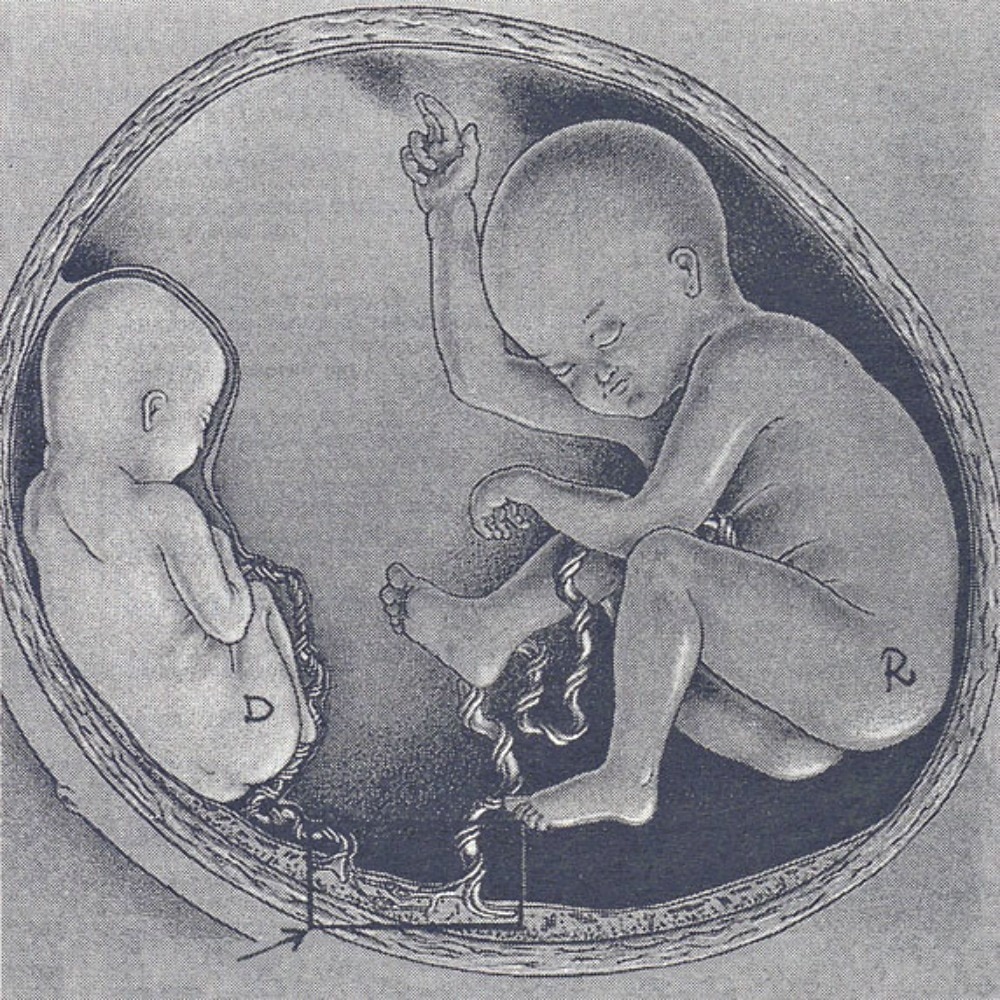

Моменты волшебства: Рождение ребенка в животе мамы

Раздел: Фотозарисовки